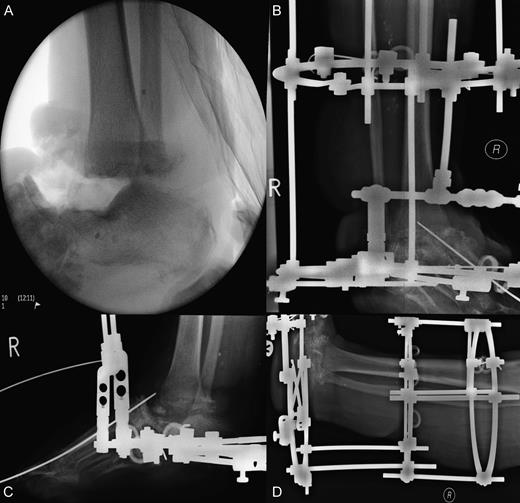

A 55-year-old woman presented with an open 3C Gustilo–Anderson fracture. Her medical history included rheumatoid arthritis, osteoarthritis, ischaemic heart disease, diabetes mellitus and asthma. Soft tissues were closed using a free flap from the left thigh and a flap from the right lower limb. Bony injury was treated with open reduction internal fixation with screw fixation of the first and third metatarsals into the talus with restoration of the medial and middle columns achieved using cannulated screws. Additional stability was achieved by plate fixation of the medial and lateral columns (Fig. 1). The treatment was deemed successful, and the patient was discharged.

Open 3C Gustilo–Anderson injury. (A and B) Theatre images of open 3C Gustilo–Anderson fracture. (C and D) Radiographs illustrating open reduction internal fixation (ORIF) (screw fixation of the first and third metatarsals into the talus). The ORIF using cannulated screws allowed restoration of the medial and middle columns of the foot. Plate fixation of the medial and lateral column was conducted to achieve additional stability.